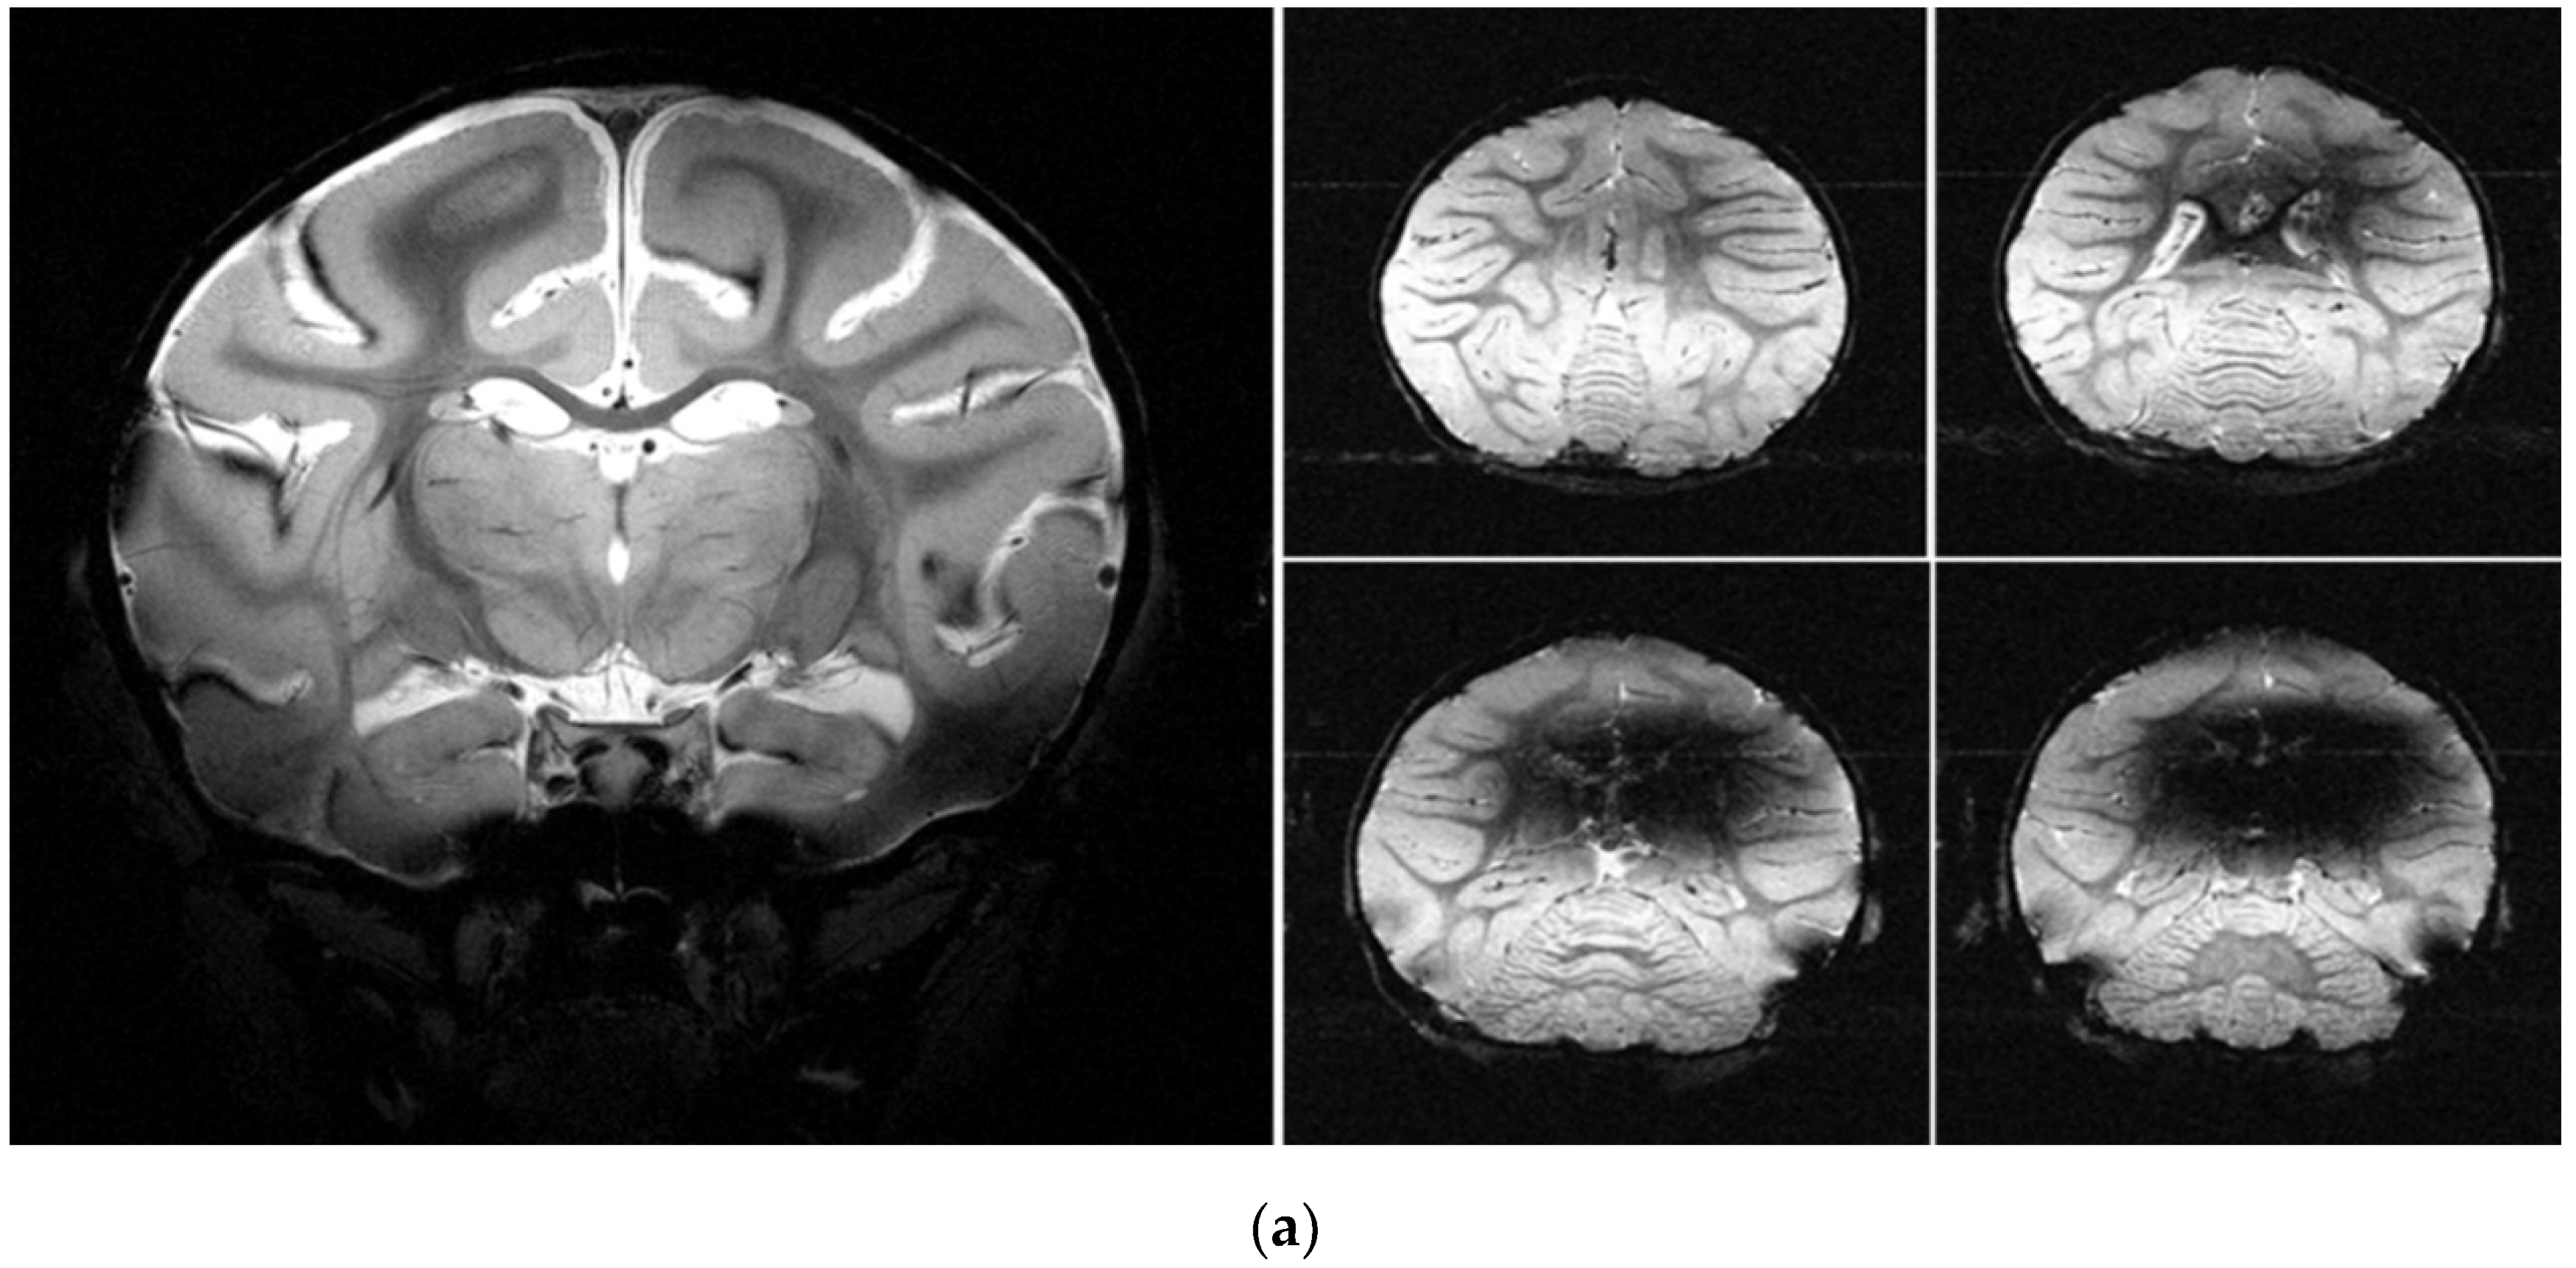

3.5. MRI